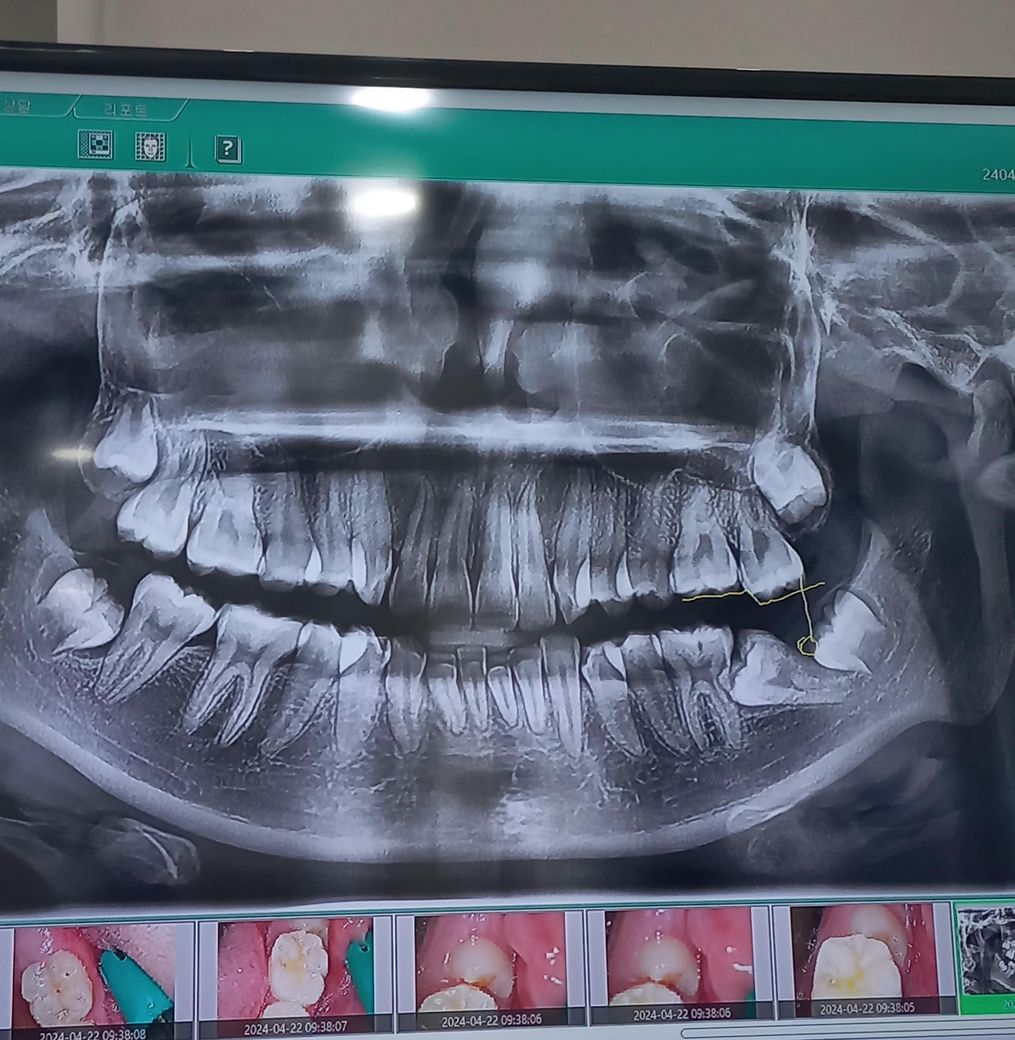

말그대로 입니다 제가 한번 입안옆쪽이 아파서 병원에 갔는데 영구치가 보시는 봐와같이 누워서 자라다가 끼었다고 해야하나? 멈췄어요. 병원에서 영구치를 어른때 뽑아서 임플란트를 해야한다고 하는데 맞나요..? 현재 지금 옆피부안쪽이 영구치 어금니가 중간에 끼여서 멈췄는데 위에 어금니가 계속 자라는데 그것 때문에ㅜ옆에 쓸려서 아픈것 같아요 영구치를 뽑아서 임플란트를 해야하나요..? 그리고 어떻게하면 좋을까요 혹시 사랑니는 없죠..?

제가 아파서 갔을때 찍은 사진인데 노란색으로 표시된것이 기울려져 있고 위에 어금니가 계속자라고 있는 것 같아요

2번째 어금니가 누어있는 상태입니다. 혹시 누어있는 어금니를 교정으로 당겨 바로 세울 수도 있으니 다른치과에서도 상담 받기를 추천합니다. 사랑니는 누어있는 어금니 바로 뒤의 치아입니다. 누워있는 어금니를 빼게 되면 사랑니를 앞으로 당기는 방법도 있습니다.

3. 사랑니 양쪽 위아래 하나씩 총 4개 있습니다. 세번째 큰 어금니가 사랑니입니다.

사랑니도 4개가 다 있는거 같고 영구치가 맹출장애가 잇는거 같습니다. 교정과를 가셔서 교정적으로 치료를 할수 잇으면 교정적으로 치료를 한번 해볼것같습니다.